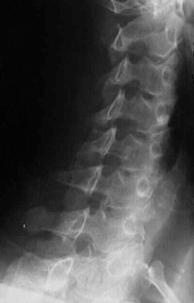

FRACTURA - LUXATIE T12 FRACTURA COMPLEXA DE COLOANA

VERTEBRALA LOMBARA